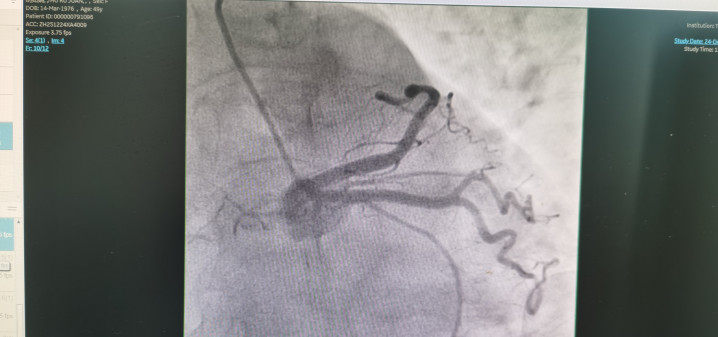

冠状动脉造影